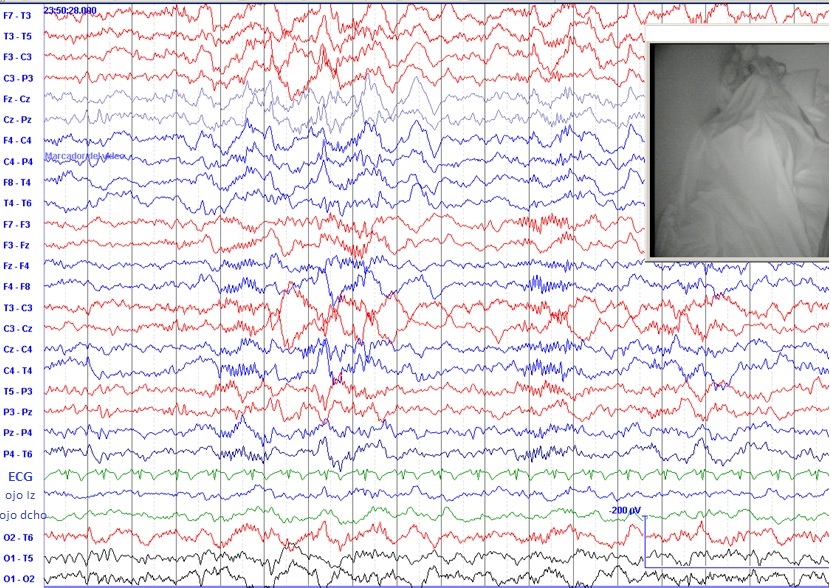

Posteriormente, en 1953, Nathaniel Kleitman descubrió que el sueño nocturno era de dos tipos: pasivo o NREM (sin movimientos oculares rápidos); y activo o REM (con movimientos oculares rápidos) Figuras 1 y 2 .

Al estudiar entonces las crisis epilépticas que se producían durante la noche se vio que el 95 % de ellas ocurrían durante el sueño pasivo o sueño NREM. El sueño NREM está formado a su vez por fases de sueño más o menos” profundo”. En aquel entonces se clasificaban (según el grado de profundidad) en fase NREM-I; NREM-II; NREM-III; y la más profunda de todas, NREM-IV. Se observó que casi todas las crisis epilépticas ocurridas durante el sueño aparecían en las fases NREM-I y NREM-II.

Posteriores estudios han confirmado la casi ausencia de crisis epilépticas durante el sueño activo o REM.

Como el sueño NREM está formado por ondas más sincronizadas que el sueño REM, que se llamó “sueño de la actividad electroencefalográfica desincronizada”, siempre se ha pensado que la desincronización del EEG sería un factor protector frente a las crisis epilépticas.